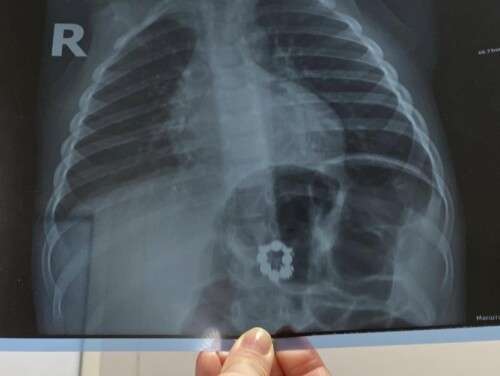

Лікували застуду: на рентген-знімку в шлунку 3-річного малюка виявили 8 магнітів

Маг­ні­ти у три­річ­но­го хлоп­чи­ка ви­яви­ли ви­пад­ко­во. Бать­ки звер­ну­ли­ся до лі­ка­ря, ко­ли ди­ти­на зас­ту­ди­ла­ся. Під час об­сте­жен­ня ма­лю­ка у пе­ді­ат­ра, лі­кар приз­на­чив рен­тген-зні­мок, на яко­му по­ба­чи­ли неп­ри­єм­ну зна­хід­ку — 8 маг­ні­тів, зам­кну­тих в ко­ло.

«При до­об­сте­жен­ні бу­ло ви­яв­ле­но чо­ти­ри маг­ні­ти в шлун­ку, а реш­ту — по­за ним. Ко­ман­да фа­хів­ців ур­ген­тної хі­рур­гії та ен­доско­пії ви­лу­чи­ли сто­рон­ні пред­ме­ти. Час­ти­ну маг­ні­тів вда­ло­ся ви­лу­чи­ли ен­доско­піч­но, ін­ші — з до­по­мо­гою хі­рур­гічно­го втру­чан­ня (ла­па­ро­то­мії)», — по­ві­дом­ляє На­ці­ональ­на ди­тя­ча спе­ці­алі­зо­ва­на лі­кар­ня «Ох­матдит» МОЗ Ук­ра­їни.

- Маг­ні­ти пе­ре­бу­ва­ли в ста­ні роз­па­ду і зна­хо­ди­ли­ся в шлун­ку ма­лю­ка до­во­лі три­ва­лий час, мож­ли­во близь­ко мі­ся­ця. За цей пе­рі­од ви­ник­ла пер­фо­ра­ція між шлун­ком та тон­кою киш­кою.